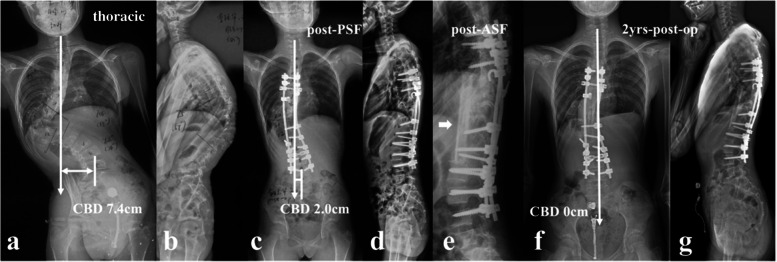

All the recruited patients were stratified according to the location of dystrophic curve apex: thoracic group, 4 cases (26.7%) (Fig. 1a, b); thoracolumbar/lumbar group, 11 cases (73.3%) (Fig. 1c, d). Among them, 1 patient in thoracic group and 3 patients in thoracolumbar/lumbar group received staged surgery with combined posterior-anterior or anterior- posterior approach (Table 1), while the rest 11 patients (73.3%) underwent posterior-only spinal instrumentation and fusion. Supplementary anterior fusion utilizing structural fibular allograft (2 patients) (Figs. 2, 8) or autogenous rib grafts (1 patient) (Fig. 3) was applied when the pedicle screw density in the apical region was distinctively low due to pedicle dystrophy disabling screw insertion. Stage 1 anterior release involving intervertebral disc resection and autogenous rib grafting was performed in 1 patient of thoracolumbar/lumbar group, followed by skull-femoral traction for 2 weeks and subsequent stage 2 posterior spinal correction and fusion.

The present study represented a homogeneous case series of dystrophic NF1 patients with convex trunk shift, and the incidence reached 8.4%. The stratification of distinguishing thoracic from thoracolumbar/lumbar CCI was important, as the incidence of immediate post-op CCI (≥3 cm) was 0.0 and 63.6% for thoracic and thoracolumbar/lumbar groups, respectively. This separation was essential because of its quite different prognosis. The likely mechanism was that the thoracic CCI was usually associated with sufficient distal non-dystrophic pedicles and reliable distal screw purchases to achieve sufficient correction of distal fractional curve and subsequently a horizontal takeoff (Fig. 5). For thoracolumbar/lumbar CCI, limited and unreliable distal screw purchases were inclined to achieve poor correction of lumbosacral fractional curve and subsequently leave residual takeoff angle, increasing the risk of failure of coronal rebalance (Fig. 6).

Based on the lessons learned from this rare case series, tips for implementing better correction maneuvers when treating this particular patient group were summarized. Rod insertion with derotation and compression maneuvers firstly on the convex side was well known to be beneficial for correction of main curve. However, over correction was easy to occur with simultaneous reverse tilt and translation of UIV to the convex side, resulting in inadvertent aggravation of CCI, particularly for those with thoracolumbar/lumbar apex and vertical proximal hemi-curve. Contrarily, if the rod was firstly inserted on the concave side using translation rather than derotation and cantilever as main correction technique, the risk of over correction of main curve was relatively small, reducing the risk of CCI aggravation. The position of UIV, being represented by its tilt and translation, was of valuable information in evaluating whether or not the coronal rebalance failed intraoperatively. If the UIV tilt and translate to convex side, fine-tuning using concave compression/convex distraction and coronal rod bending in upper hemi-curve region were beneficial to increase the coronal compensation (Fig. 7). Finally, a vertical morphology of instrumentation being confirmed by intraoperative fluoroscopy was essential for reliable coronal realignment.

The follow-up data revealed that patients in the imbalanced group experienced spontaneous improvement of CCI over time (Ratio of CBD < 3 cm: 100%). This usually resulted in an acceptable but not satisfying coronal alignment because residual tilting of the instrumentation mass and/or junctional angulation centering around LIV existed (Fig. 8), and might result in implant failure (Fig. 5). Both distal compensation (decreased tilting of the instrumentation mass and LIV to the convex side) and proximal compensation (increased UIV disc angle) accounted for such coronal rebalance, and our data was suggestive that the distal compensation was the mainstay compensative mechanism. This was in line with Bao’s previous finding that LIV at L4 or higher was correlated to a higher chance of spontaneous coronal rebalance [ref. 7].